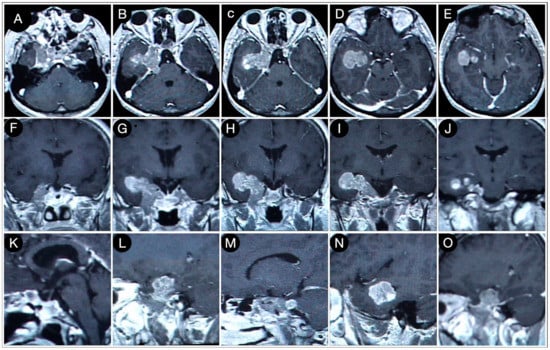

Case #1: Infradiaphragmantic Tumor with Middle Fossa Involvement through the Cavernous Sinus

3.2.1. Case #2: Involvement of the Anterior Skull Base

3.2.2. Case #3: Paramedian Pattern of Growth with Parenchymal Invasion

3.3.1. Case #4: Involvement of the Middle Skull Base with Parenchymal Invasion

3.3.2. Case #5: Extension beyond the Lateral Wall of the Cavernous Sinus

3.3.3. Case #6: Encasement of the Posterior Communicating and Anterior Choroidal Artery

Case #7: Encasement of the Paraclinoid and Supraclinoid Internal Carotid Artery

Case #8: Aggressive ACTH Tumor with Multiple Recurrences